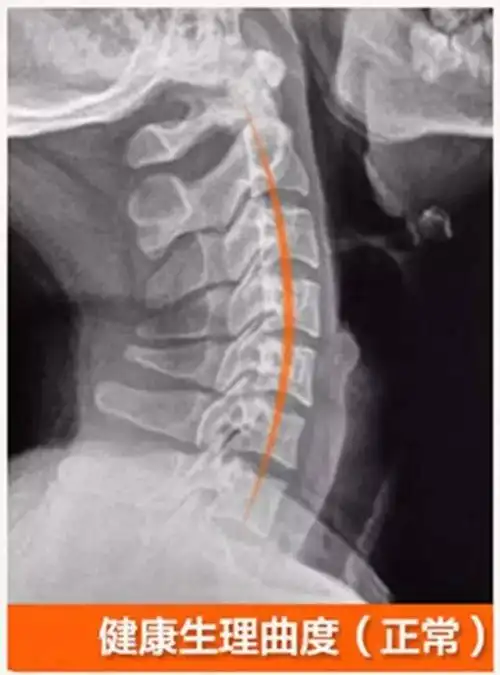

颈椎生理曲度消失是怎么还回事?能恢复吗?(一)

1.颈椎曲度

正常的人体脊椎生理弯曲图

注意一下你的颈椎弧度是否正确